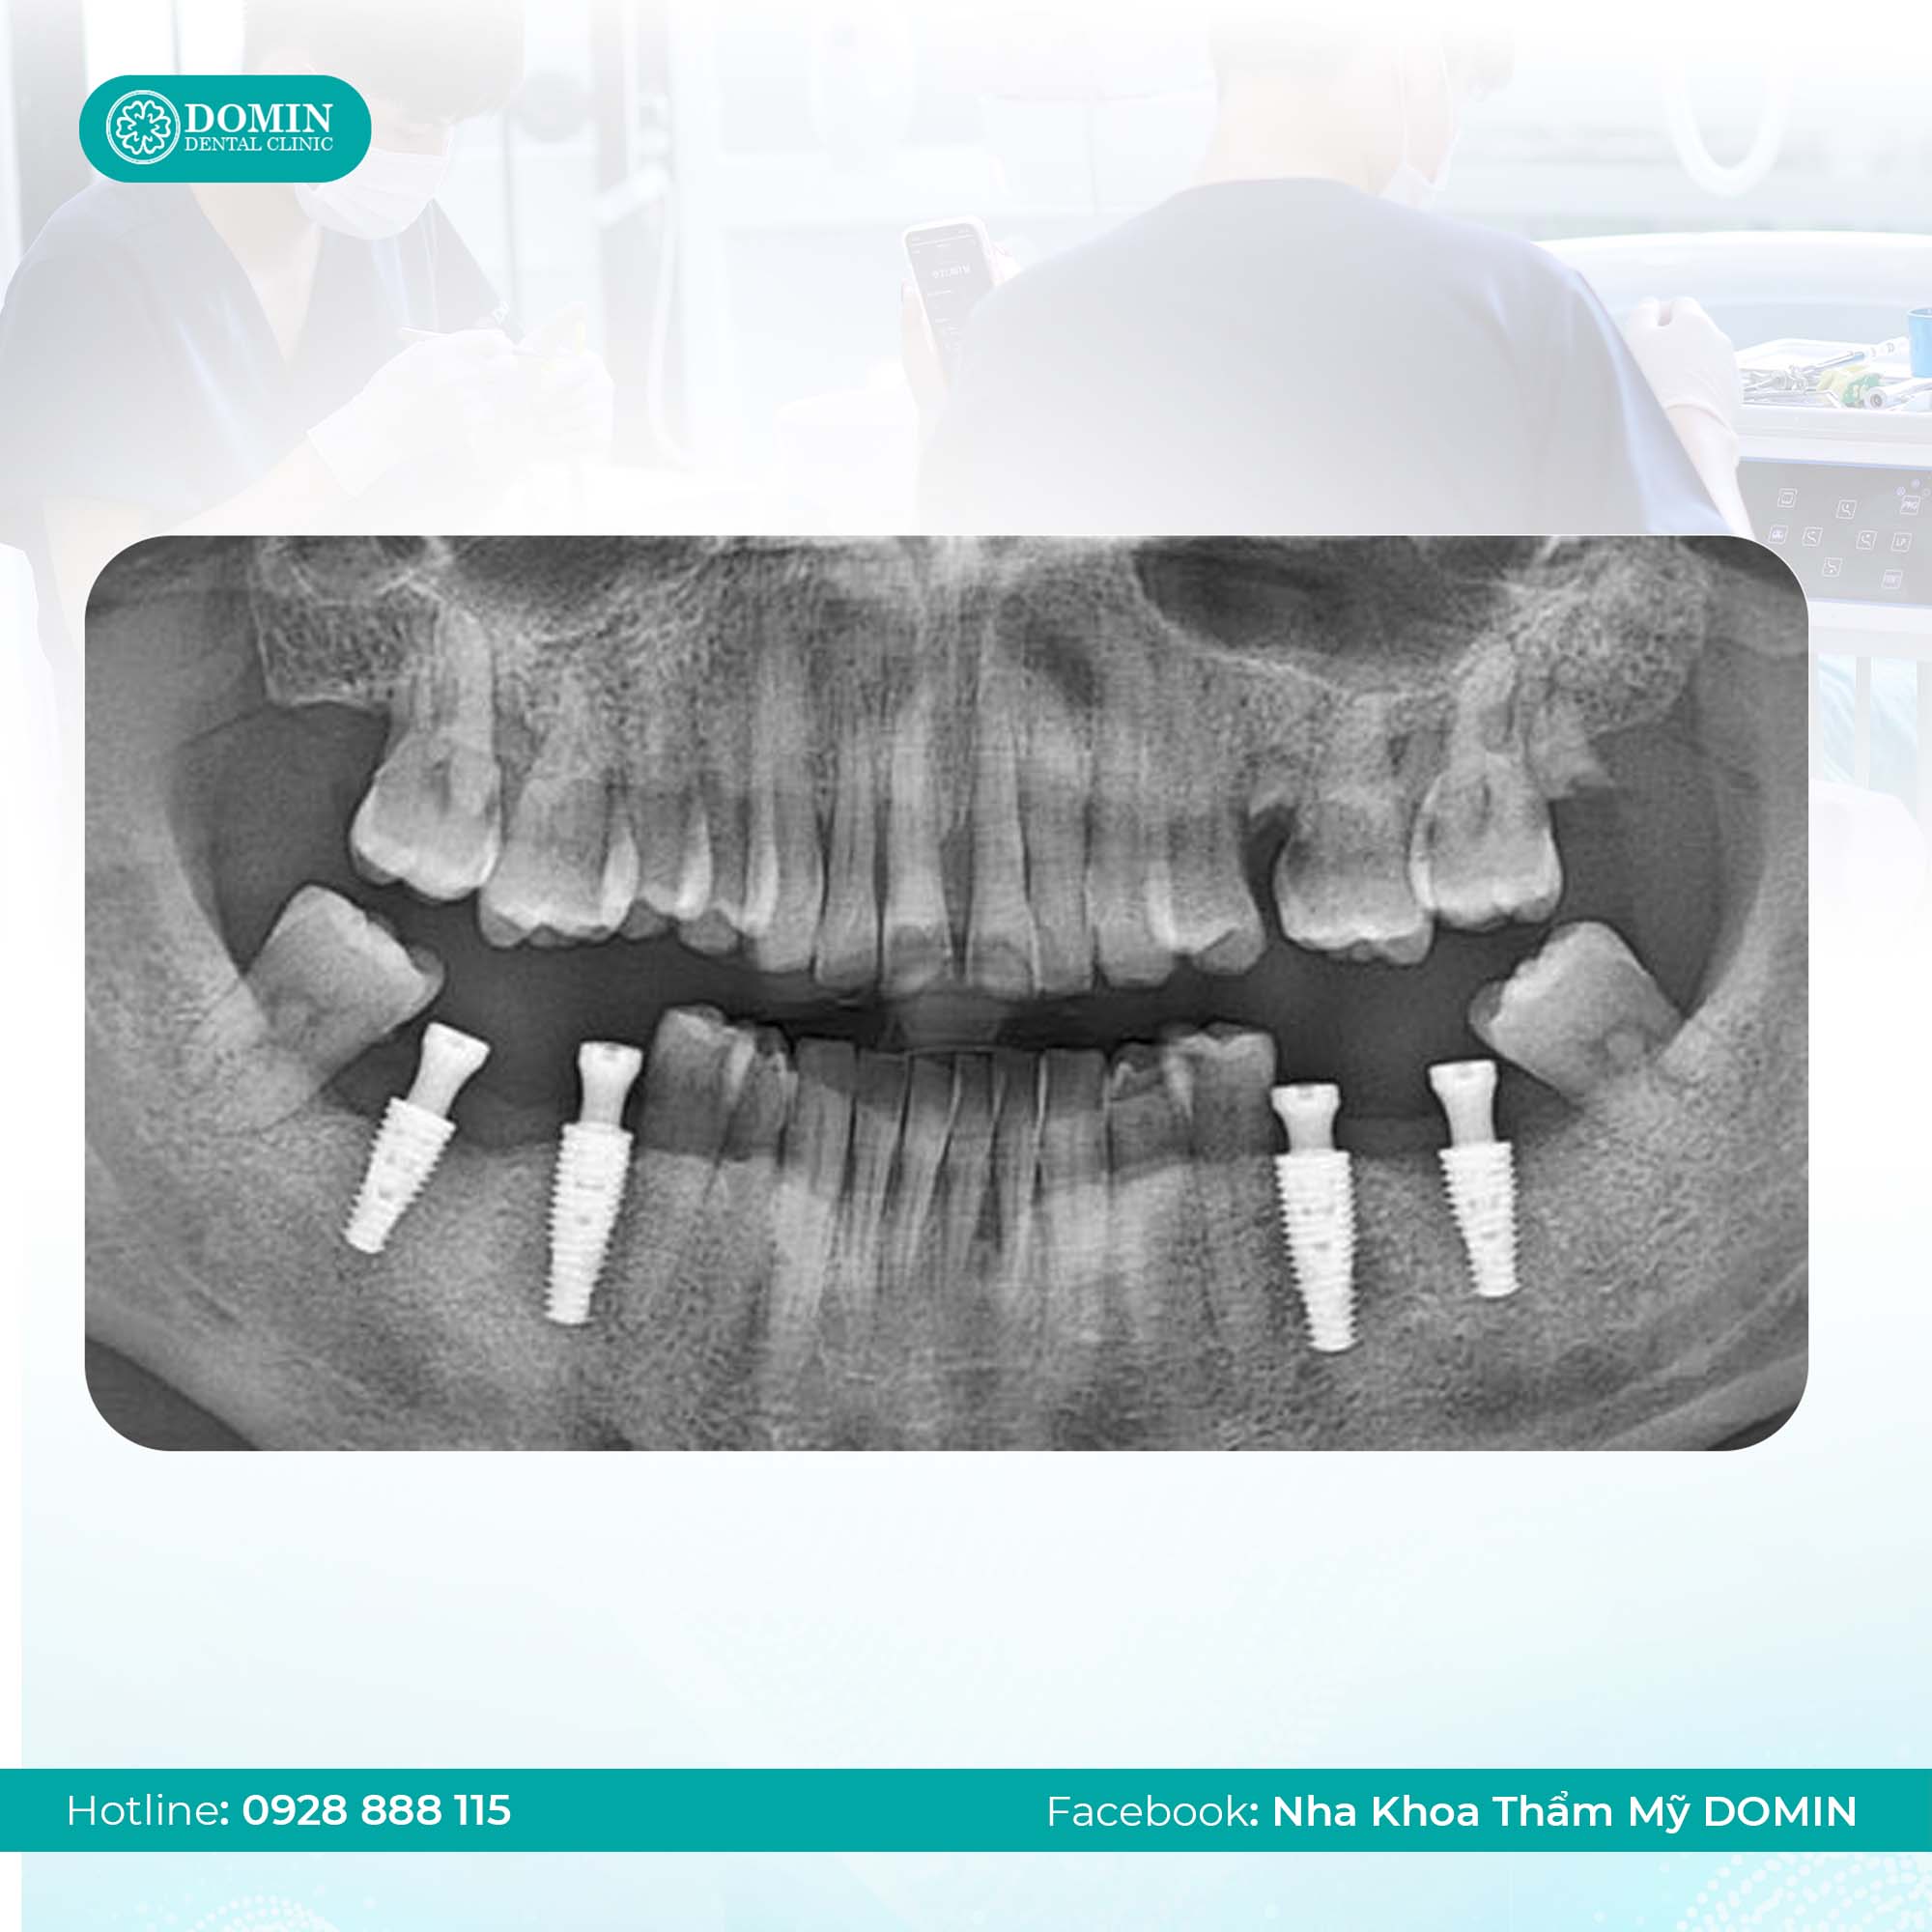

- Chụp phim CT Cone Beam 3D trước khi trồng để xác định vị trí thần kinh.

- Cặn chụp CT Cone Beam 3D trước khi trồng.